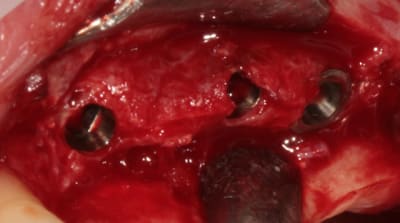

mise en place du conique lisse

et un et deux et trois

après les implants lisses coniques il faut passer aux lisses Axioms

Bonjour mes CHERS AMIS, ouverture à 5 mois, et comme vous êtes sympas, je fais un lambeau (la patiente me pardonnera)

deux trois photos pour montrer que crédulité et optimise ne vont pas de pair....